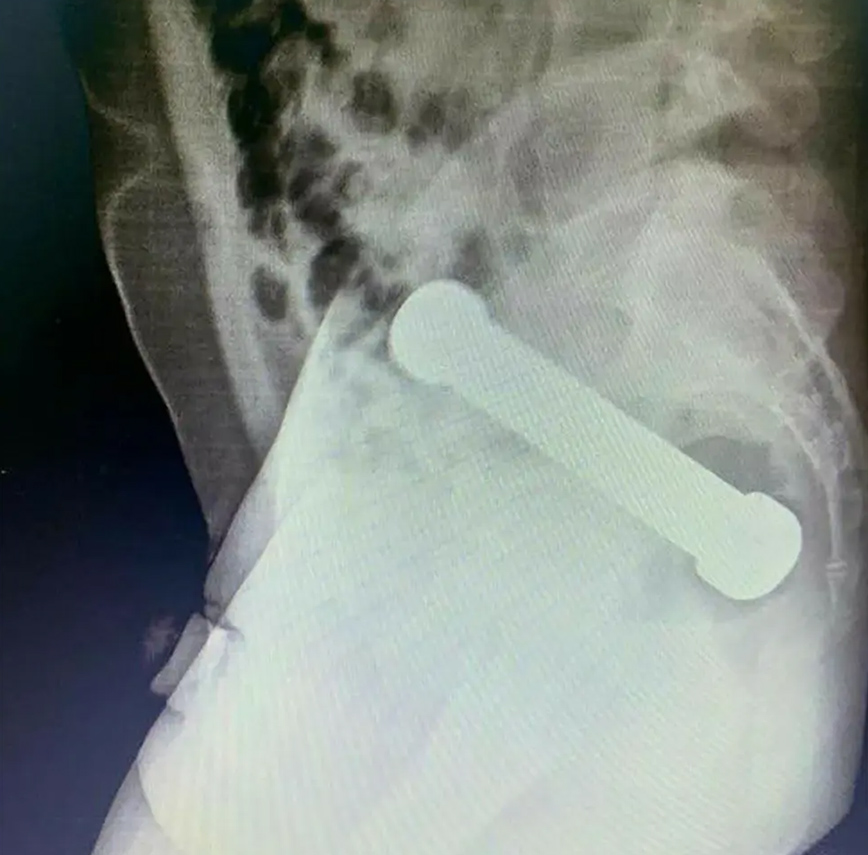

Αφού η αρχική πρωκτική εξέταση δεν αποκάλυψε τίποτα, οι γιατροί αποφάσισαν να σαρώσουν την περιοχή με ακτινογραφία. Ανακάλυψαν έναν αλτήρα μήκους 8 ιντσών που είχε σφηνωθεί στη διασταύρωση του παχέος εντέρου και του ορθού σαν ένα δυσκίνητο σεξουαλικό παιχνίδι.